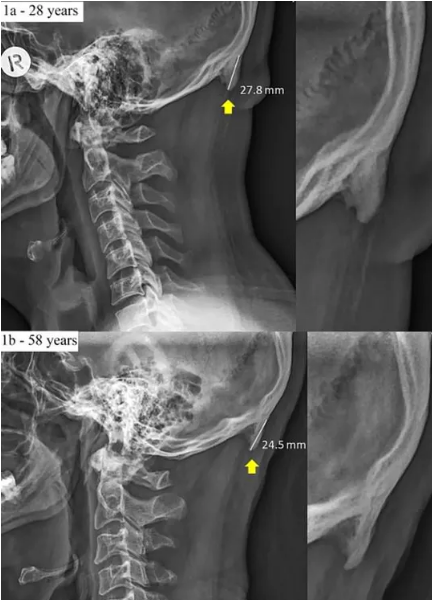

Trong phim X-quang đã ghi nhận một người 28 tuổi có khối u chẩm ngoài mở rộng so với một người 58 tuổi có cấu trúc xương bình thường, có thể thấy một kết cấu nhô ra thêm đến 3 mm ở người 28 tuổi. Tình trạng có thể nghiêm trọng hơn ở những người thế hệ sau, nếu họ ghiền smartphone từ khi còn là một đứa trẻ.

Khối u chẩm ngoài mở rộng có thể mô tả như một chiếc gai, một cục xương thừa lạ lùng mọc nối dài thêm ở khu vực đáy sọ, gần thùy chẩm, tức phía gáy của bạn. Theo khảo sát, chúng thường xuất hiện ở nhóm người từ 18-30 tuổi (lứa tuổi thường dành nhiều thời gian cho smartphone).

Hình chẩn đoán ở người 28 tuổi vẫn có mầm mống của gai xương